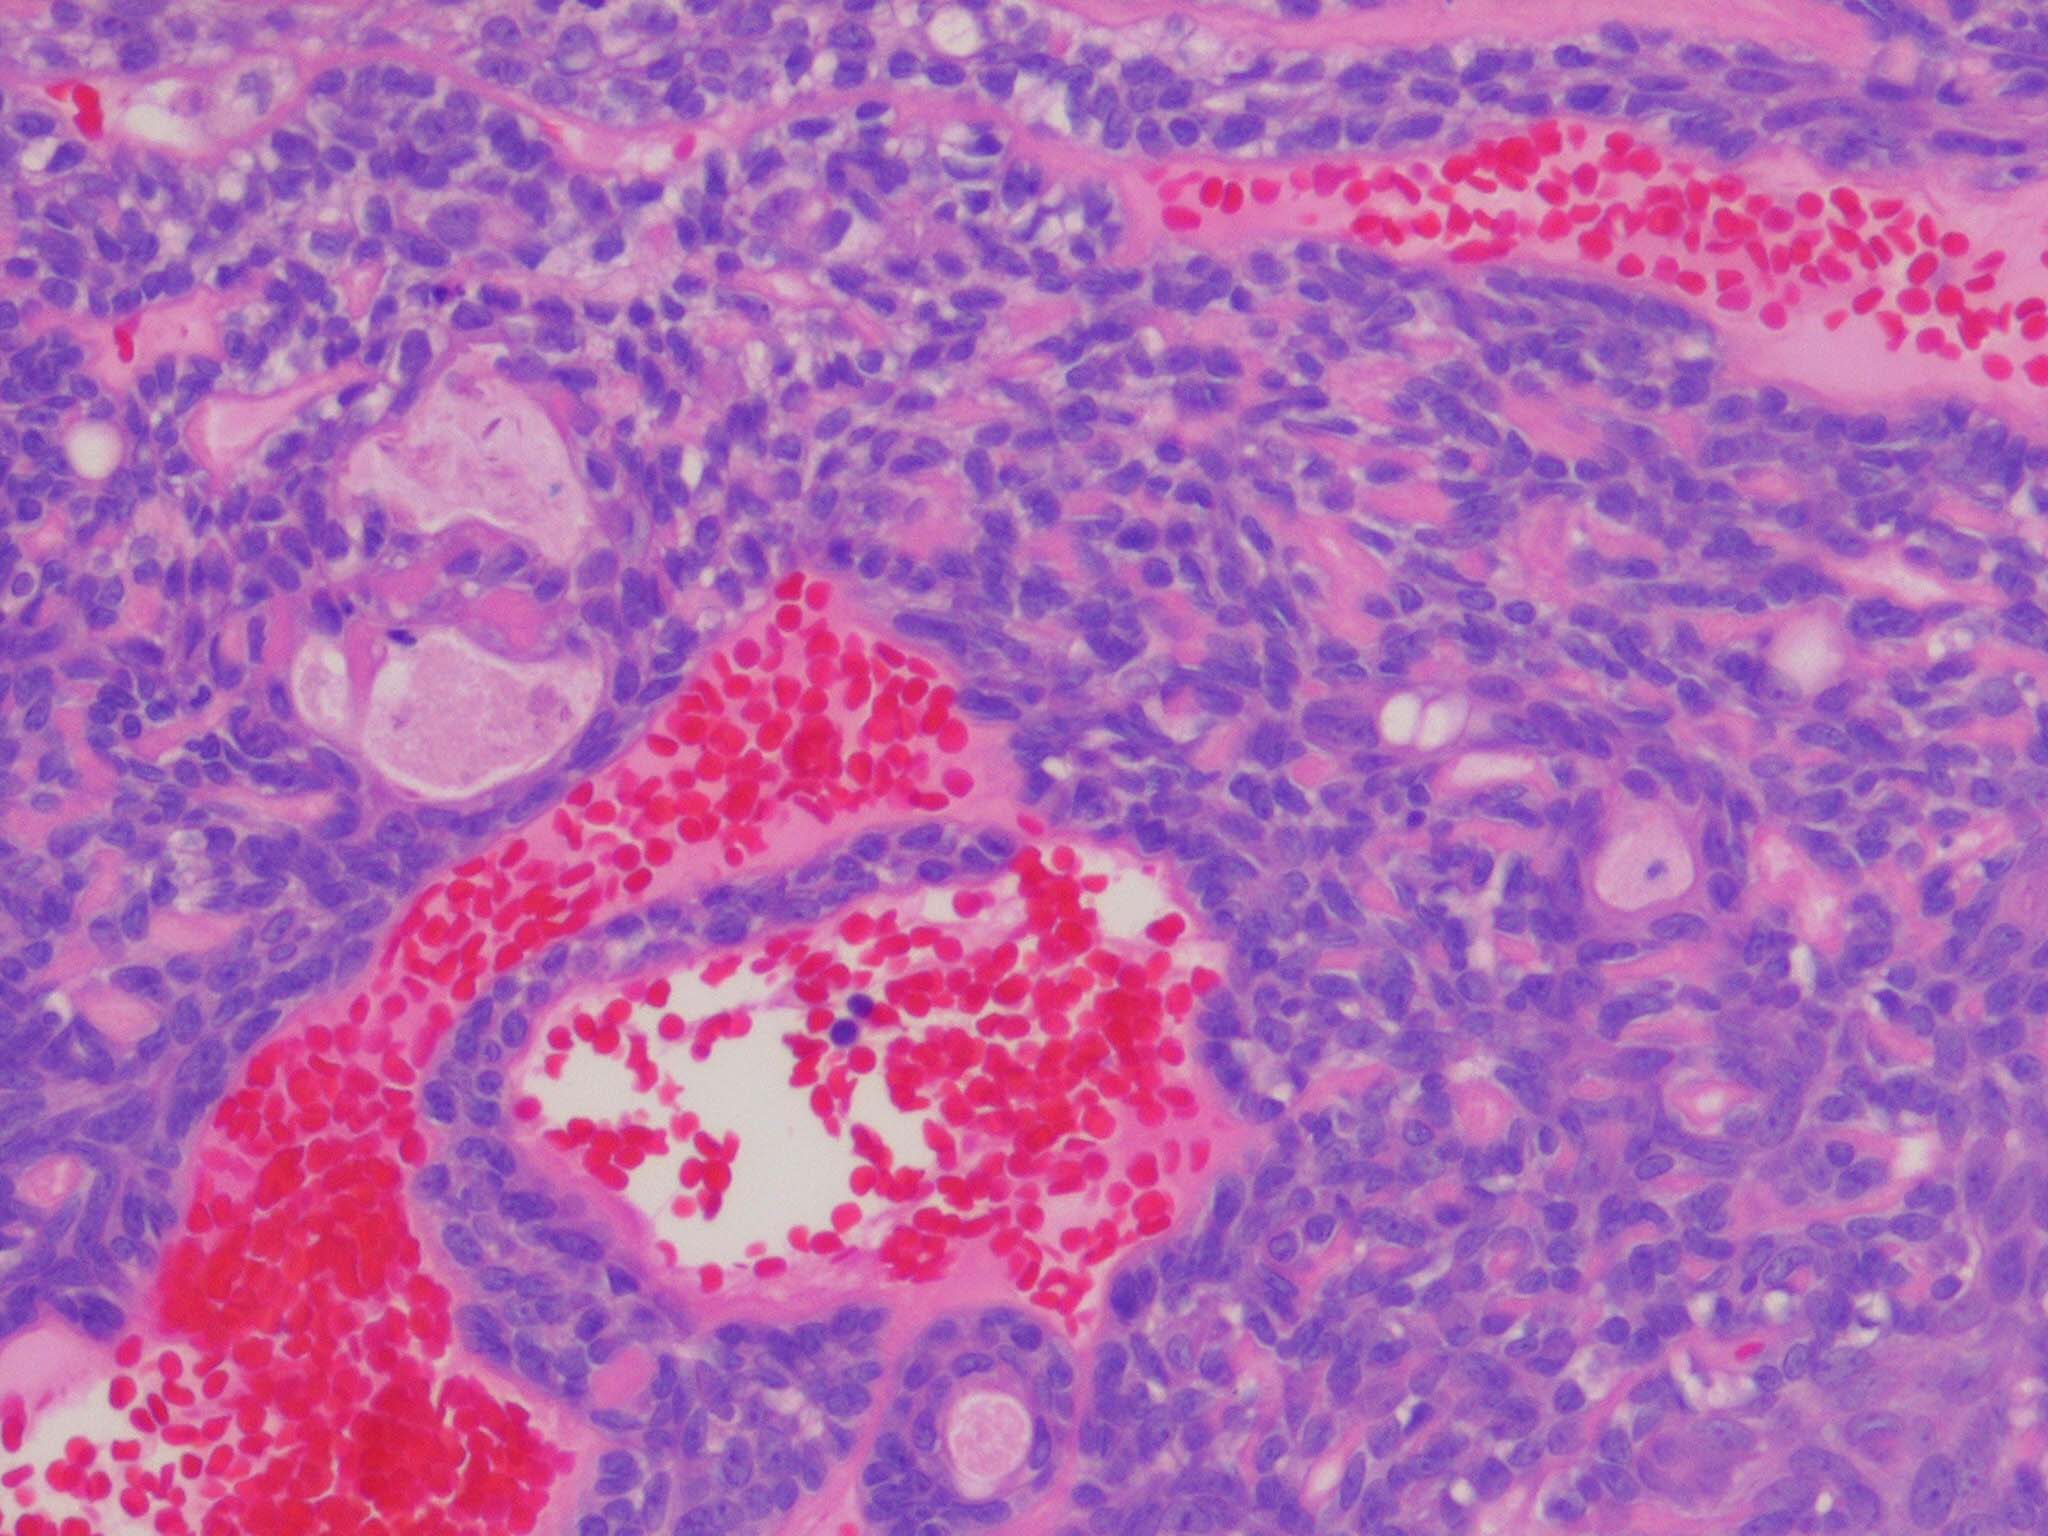

Spiradenoma=ورم غدي عرقي

OLYMPUS DIGITAL CAMERA